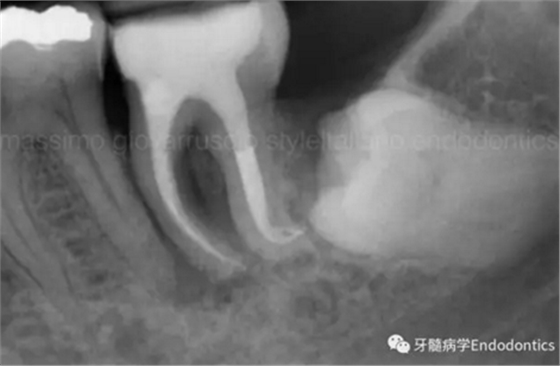

圖4.根尖孔通常比10號K銼大,因此感到任何阻力時(shí)可能是因?yàn)楦艿膹澢虿灰?guī)則。因此,有效的建立可重復(fù)的引導(dǎo)通道的方法應(yīng)是使用10號K銼逐步擴(kuò)大開放根管,此時(shí)也將產(chǎn)生臺階或根管堵塞的可能性降到最低。

圖5.探查時(shí)銼不能向根尖方向用力,因?yàn)樾纬膳_階的風(fēng)險(xiǎn)會顯著增加。如果銼的尖部從未卡入根管壁,是不可能形成臺階的。